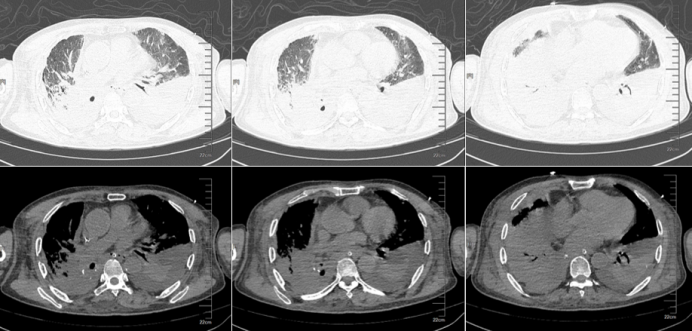

• 床旁胸片(2025-02-23):双肺渗出明显增加,且以双下肺为主(图8)

图片

8  患者床旁胸片(2025-02-23)

• 胸部CT(2025-02-28):双肺大量新发渗出,病灶主要集中在双下肺,大片实变,肺不张,少量胸腔积液(图9)

9  患者胸部CT(2025-02-28)